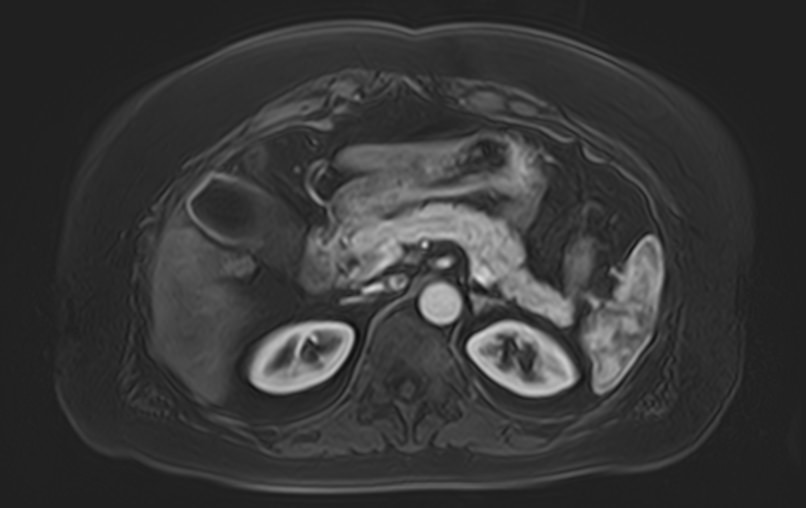

Магнитно-резонансная томография брюшной полости является наиболее информативной безопасной и эффективной методикой обследования внутренних органов. Метод позволяет проводить дифференциальную диагностику в сложных клинических случаях. Особенно это важно при противоречивых и неоднозначных данных, полученных при проведении УЗИ, рентгенографии, КТ или других обследованиях.

Методика МРТ основана на применении внешнего магнитного поля и отличается точностью и достоверностью полученных данных. Отсутствие вредного рентгеновского излучения делает процедуру безопасной и позволяет при необходимости проводить томографию несколько раз в течение короткого периода времени. Это бывает важно, например, для оценки динамики состояния патологических изменений в органах на фоне лечения.

Для расширения возможностей диагностики, при необходимости уточнения характера патологических изменений, в случае подозрения на опухолевый процесс, дополнительно применяется контрастное усиление.

Для этого в вену вводится контрастный препарат, содержащий металл гадолиний (Магневист, Гадовист, Омнискан и др). Степень и характер накопления контрастного препарата в органах и тканях позволяет различать патологические процессы. Это дает возможность, в частности, диагностировать патологические очаги минимальных размеров, что бывает особенно важно в ранней диагностике опухолей.

В клинике «Доступная медицина» МР томография проводится на новейшем высокопольном томографе экспертного класса TOSHIBA VANTAGE TITAN 1,5 Тесла. Высокая индукция магнитного поля обеспечивает повышенную четкость изображений при проведении обзорной МРТ брюшной полости, что гарантирует точность и эффективность диагностики заболеваний печени, желчного пузыря, поджелудочной железы и селезенки. Аппарат послойно сканирует исследуемую область с шагом от 1 мм в различных плоскостях, затем трансформирует результаты в трехмерные изображения превосходного качества. Для уточнения характера патологических изменений одного из органов назначается прицельная МР томография данного органа.